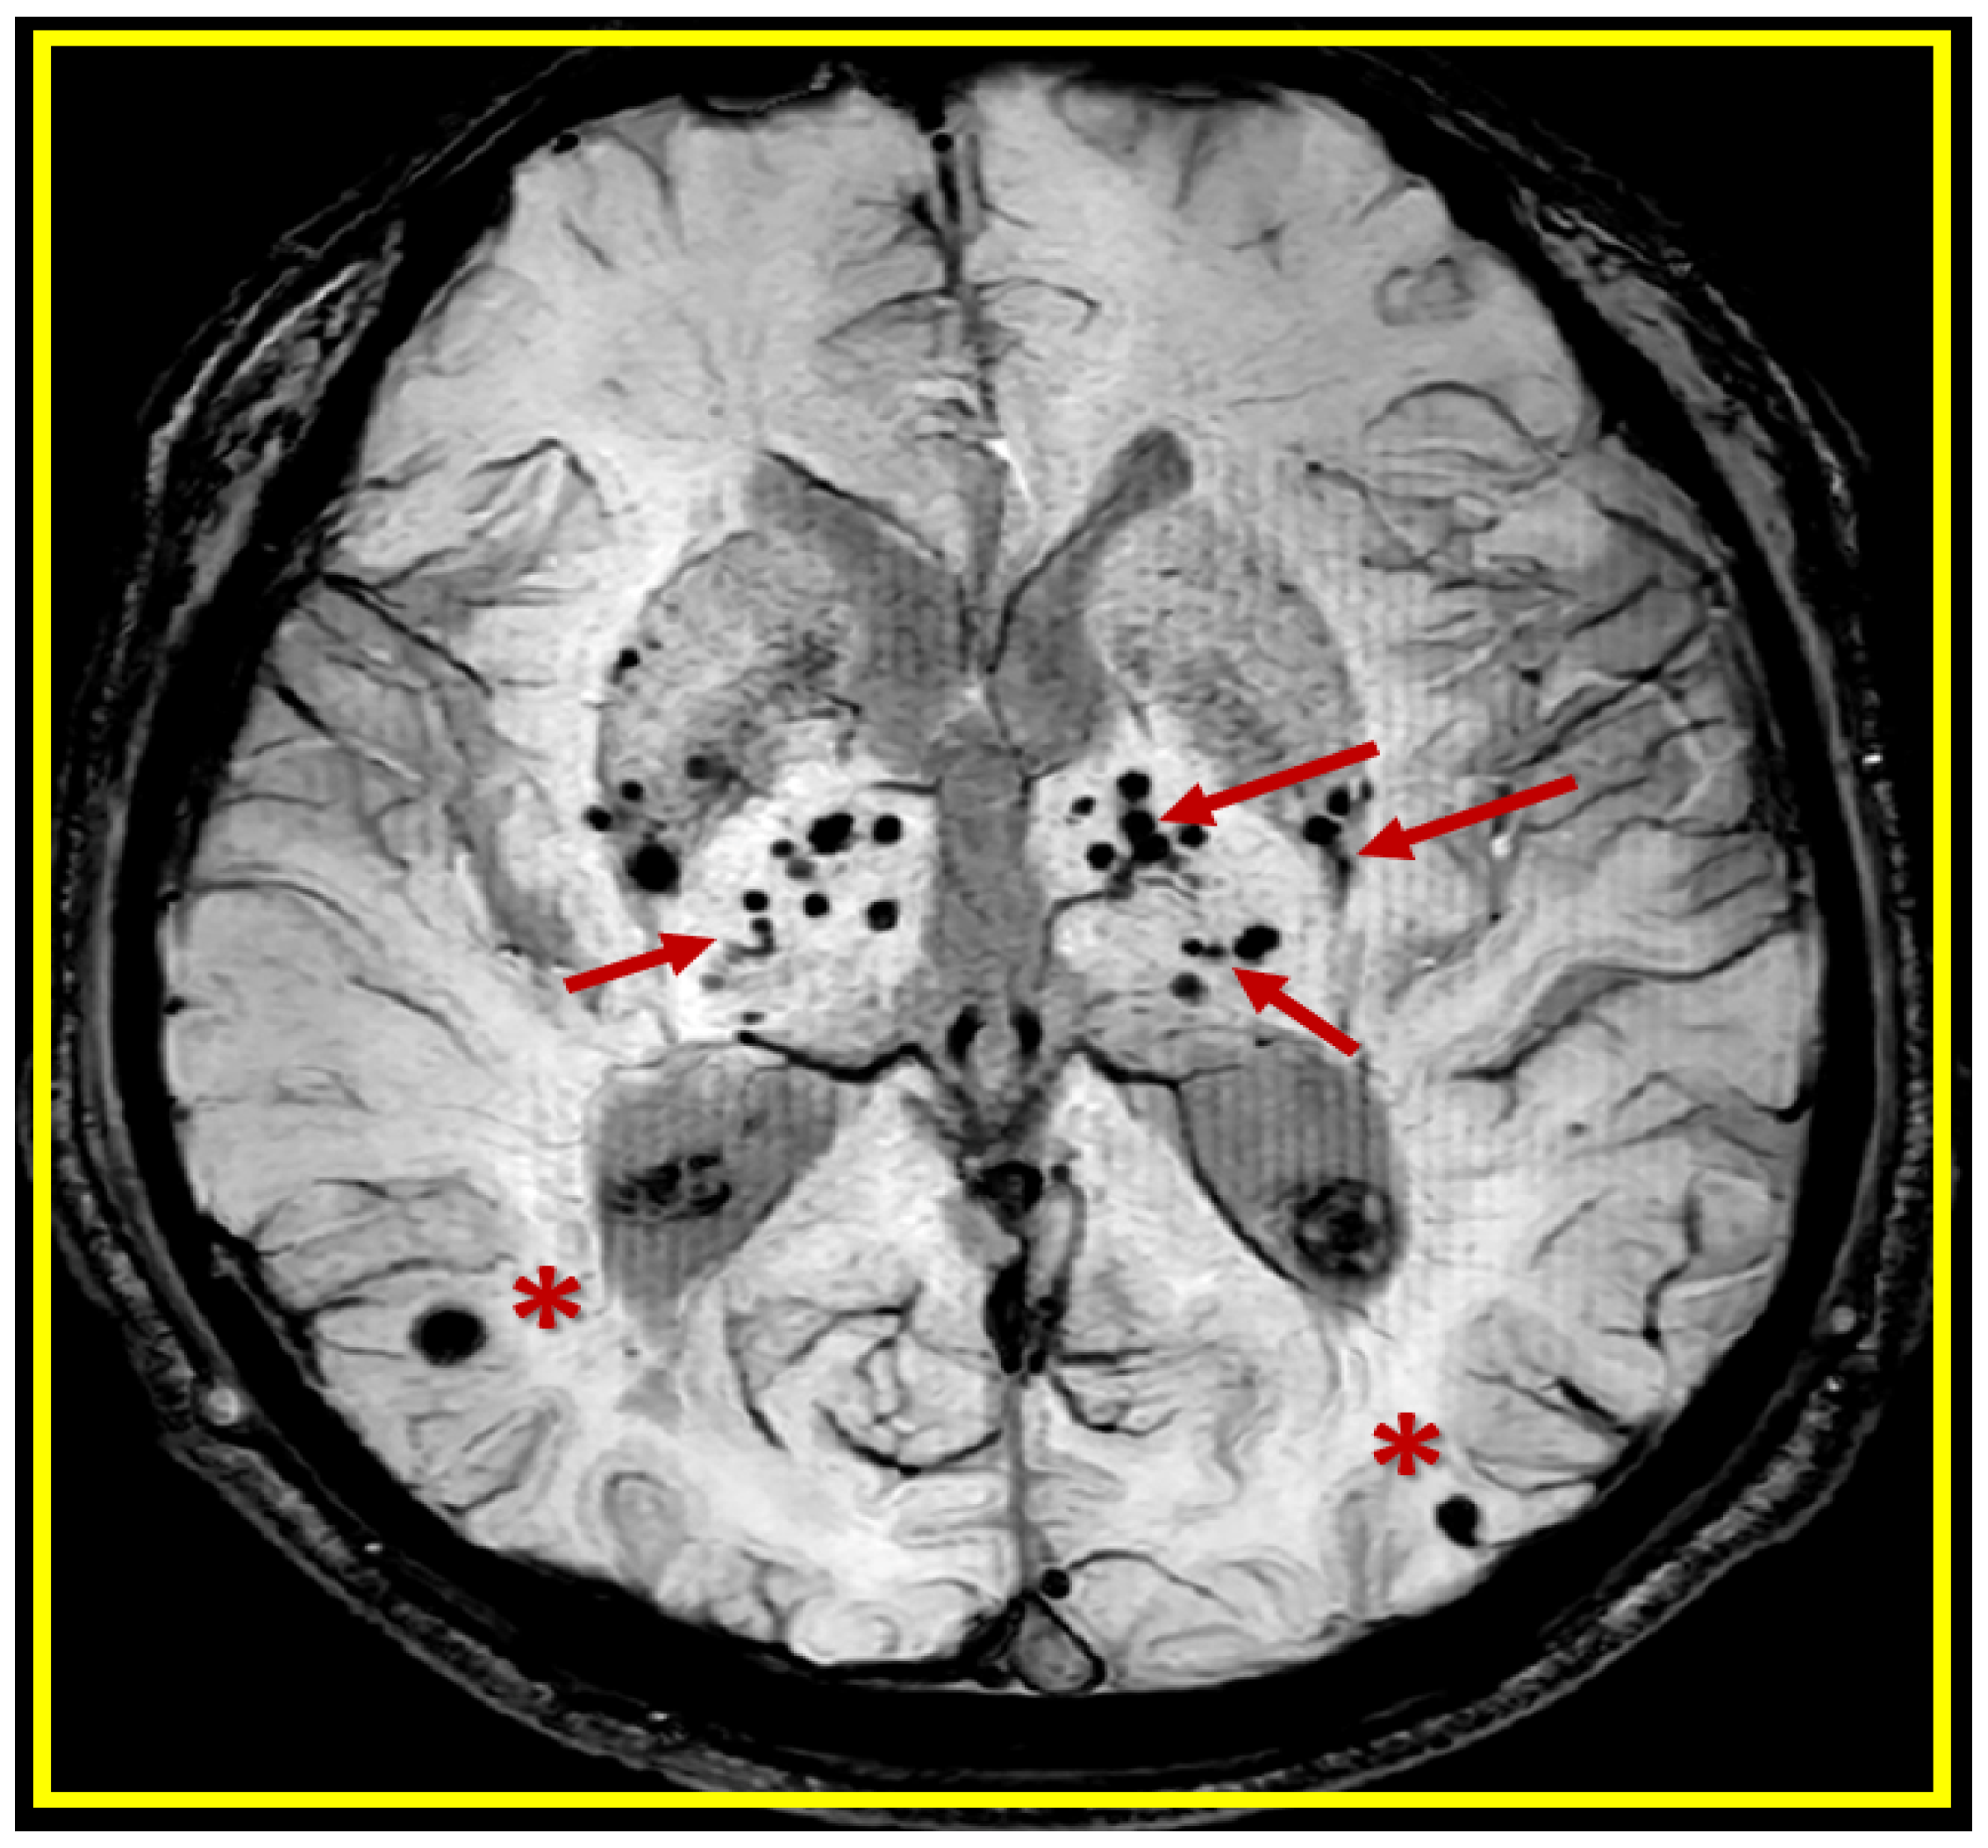

1. Introduction

2. A Possible Sequence of Events in the Development of Cerebral Microvessel Bleeds (CMBs)

2.1. Brain Endothelial Cell Activation and Dysfunction (BECact/dys)

2.2. Blood–Brain Barrier Dysfunction and/or Disruption (BBBdd) with Increased Permeability